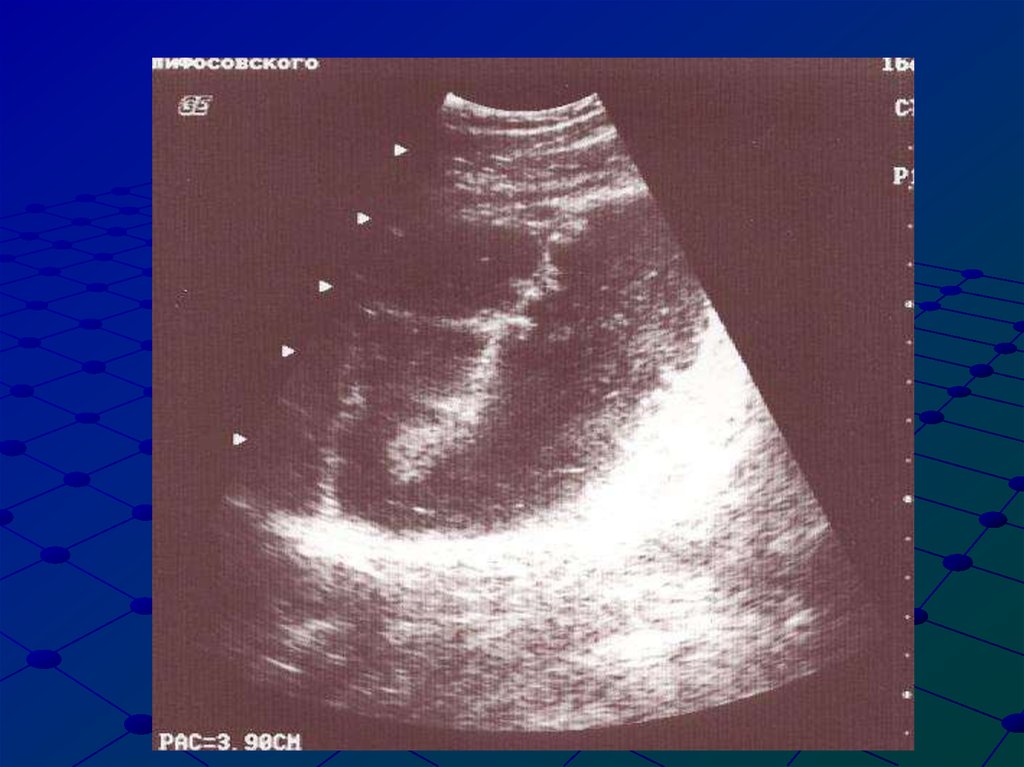

19. Тонкокишечная непроходимость, ассимметрия диаметра

22. Ультразвуковые признаки механической тонкокишечной непроходимости

Расширение просвета тонкой кишки более 3-5 см в

диаметре

Ассиметрия диаметров тонкой кишки

Толщина стенок фрагмента тонкой кишки более 3

мм / при странгуляции, ущемлении/

Депонирование жидкостного содержимого в

просвете кишки

Наличие маятнико- образного движения кишечного

содержимого

Отсутствие газа в толстой кишке

Гастростаз

Пневматизация тонкой кишки